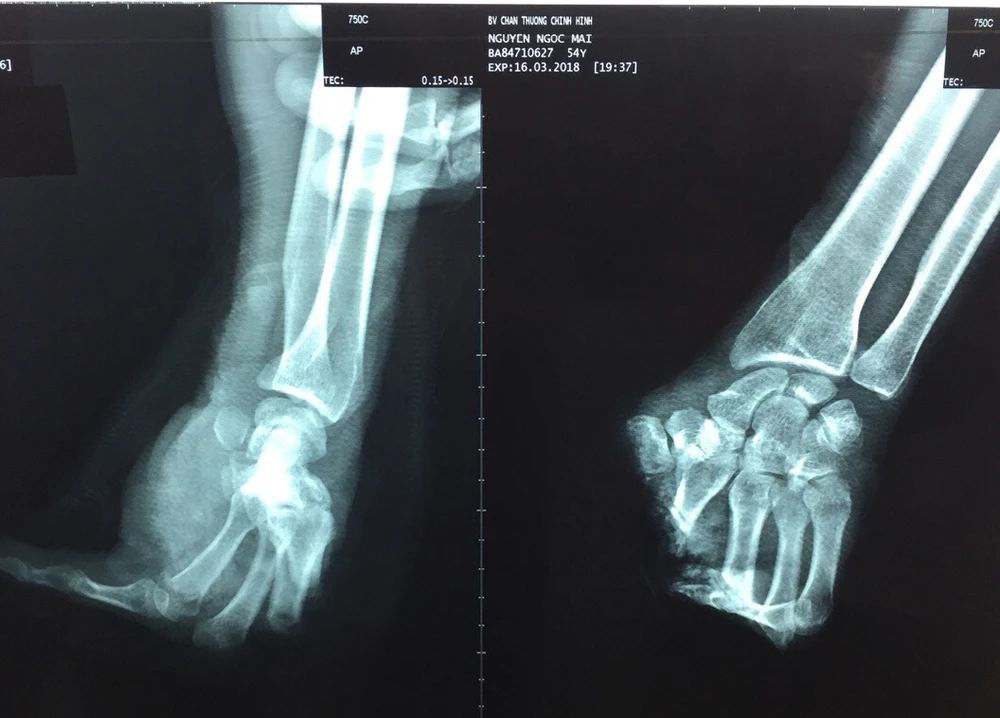

Kết quả chụp X-quang cho thấy bàn tay trái ông M. bị cắt đứt lìa. Ảnh: HÒA KHÁNH